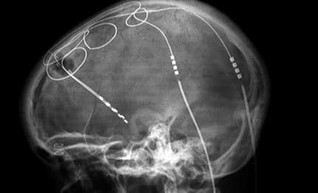

I biosensori sono già ampiamente utilizzati, ad esempio nel monitoraggio del glucosio. Possiamo ingerire una “pillola” elettronica per esplorare il funzionamento del tratto gastrointestinale. La telemetria consente di caricare sul cloud i dati delle variabili monitorate. I progressi nell’informatica e nell’IA riconoscono i modelli nelle variabili, interpretano i dati e suggeriscono i risultati senza l’intervento umano. I dispositivi impiantati possono già modificare la frequenza cardiaca, controllata dall’esterno del corpo. Gli elettrodi che forniscono una stimolazione cerebrale profonda possono controllare la pressione sanguigna in individui resistenti alle terapie e alleviare i sintomi delle malattie degenerative.